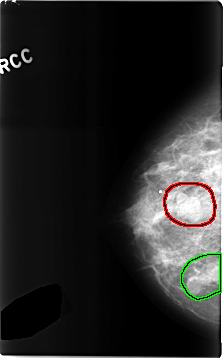

C_0306_1.RIGHT_MLO

FILE: C_0306_1.RIGHT_MLO.OVERLAY

TOTAL_ABNORMALITIES 2

ABNORMALITY 1

LESION_TYPE MASS SHAPE LOBULATED MARGINS OBSCURED

ASSESSMENT 4

SUBTLETY 5

PATHOLOGY BENIGN

TOTAL_OUTLINES 1

BOUNDARY

ABNORMALITY 2

FILE: C_0306_1.RIGHT_CC.OVERLAY

LESION_TYPE MASS SHAPE LOBULATED MARGINS CIRCUMSCRIBED